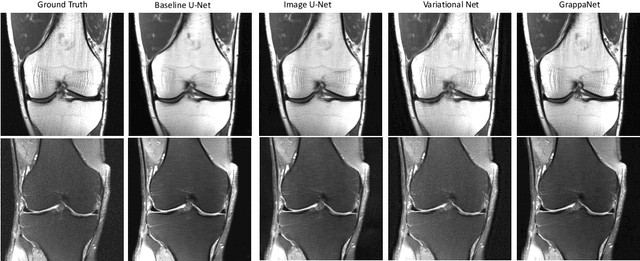

Abstract:Purpose: To advance research in the field of machine learning for MR image reconstruction with an open challenge. Methods: We provided participants with a dataset of raw k-space data from 1,594 consecutive clinical exams of the knee. The goal of the challenge was to reconstruct images from these data. In order to strike a balance between realistic data and a shallow learning curve for those not already familiar with MR image reconstruction, we ran multiple tracks for multi-coil and single-coil data. We performed a two-stage evaluation based on quantitative image metrics followed by evaluation by a panel of radiologists. The challenge ran from June to December of 2019. Results: We received a total of 33 challenge submissions. All participants chose to submit results from supervised machine learning approaches. Conclusion: The challenge led to new developments in machine learning for image reconstruction, provided insight into the current state of the art in the field, and highlighted remaining hurdles for clinical adoption.

Abstract:Magnetic Resonance Image (MRI) acquisition is an inherently slow process which has spurred the development of two different acceleration methods: acquiring multiple correlated samples simultaneously (parallel imaging) and acquiring fewer samples than necessary for traditional signal processing methods (compressed sensing). Both methods provide complementary approaches to accelerating the speed of MRI acquisition. In this paper, we present a novel method to integrate traditional parallel imaging methods into deep neural networks that is able to generate high quality reconstructions even for high acceleration factors. The proposed method, called GrappaNet, performs progressive reconstruction by first mapping the reconstruction problem to a simpler one that can be solved by a traditional parallel imaging methods using a neural network, followed by an application of a parallel imaging method, and finally fine-tuning the output with another neural network. The entire network can be trained end-to-end. We present experimental results on the recently released fastMRI dataset and show that GrappaNet can generate higher quality reconstructions than competing methods for both $4\times$ and $8\times$ acceleration.